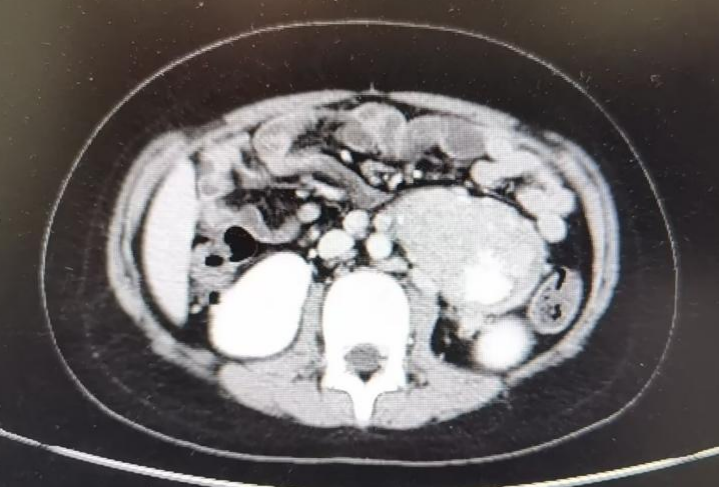

术前CT(2022.8.3)显示腹膜后肿物及淋巴结较前明显缩小。

术后病理:

神经母细胞瘤,分化差型,低度MKI;可见出血、钙化,符合化疗后反应。

区域淋巴结可见肿瘤累犯,分组如下:左肾门11/13,动静脉间2/2,主动脉旁9/10。